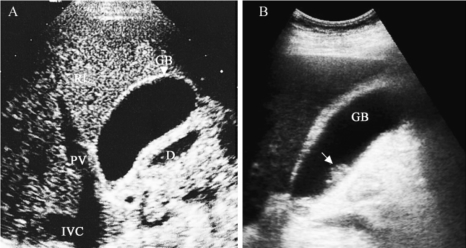

1.正常含液体的脏器 如胆囊、膀胱、心脏、血管等,周围组织-腔壁-液体之间的界面回声,腔壁的厚度。液体为无回声区(图1-12A)。当在病理情况下,含液脏器壁或液体中有异常时,正常超声图被破坏。

5.病变脏器(或组织)的回声规律 脏器或组织有病变时,病变组织与正常组织的声学特性不同,超声通过时产生不同于正常组织的回声规律,不同的病变组织声学特性及回声规律也不相同。如胆囊息肉则显示无回声区中有中等回声团为息肉的回声,息肉对超声吸收少,其后方无声影(图1-12B)。子宫前壁实质低回声区伴彩色血流增多为子宫肿瘤(图1-12D)。

图1-12 正常组织(脏器)与病理组织回声规律

A、B.含液体脏器:正常胆与胆囊息肉的声像图;C、D.实质性脏器:正常子宫与子宫肿瘤;E、F.含气脏器:正常肺多次反射与胸腔积液